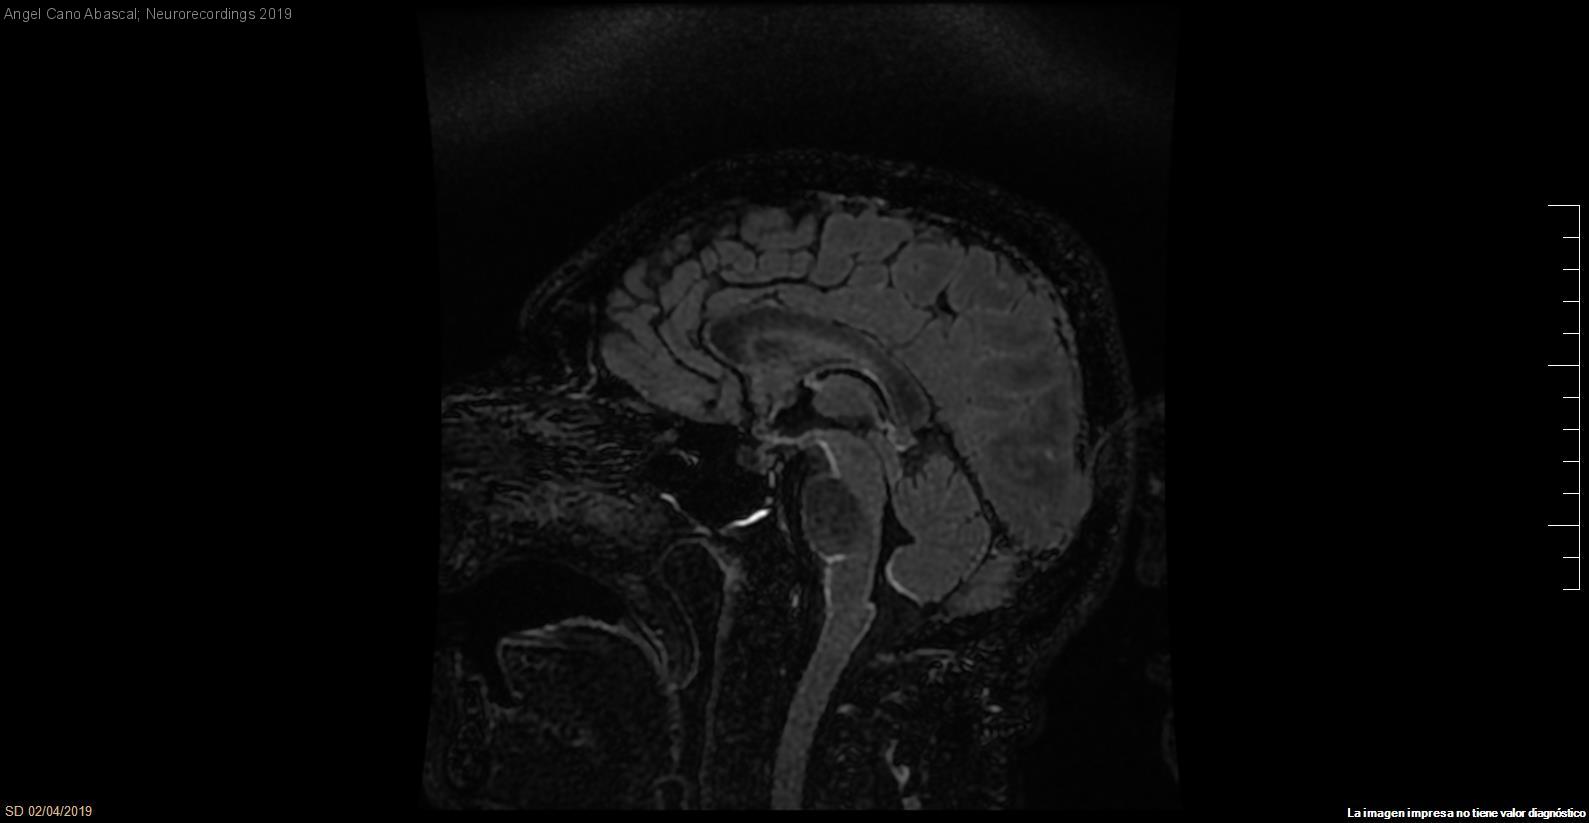

Afectación leptomeníngea secundaria a meningoencefalitis de origen tuberculoso

Diagnóstico final: Meningoencefalitis tuberculosa

Varón de 63 años en tratamiento con Infliximab por artritis reumatoide, que consulta por cuadro de 10 días de evolución de cefalea, febrícula y náuseas a lo que añade posteriormente alteración del lenguaje y fluctuación del...